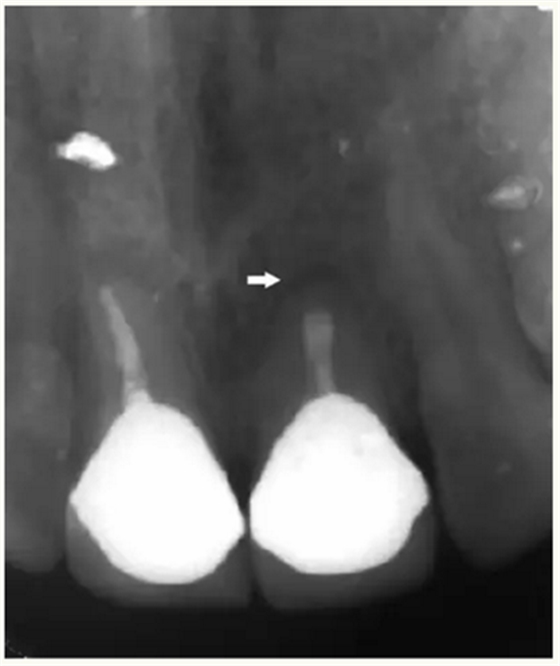

▲术后,X线显示:21根尖切除区域骨质修复,根管倒充填物完好,原牙周膜间隙增宽影消失